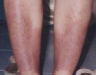

After reviewing the case The patient was asked to take one more dose of Lycopodium 1m on 19th march 2001. Here is the photographs of 27th march 2001 indicating the condition of her Legs.

By the time the disease has started to tend down. This was the condition by 16th April 2001. She was having lot of itching but there was no oozing, a gentle red color was left over.